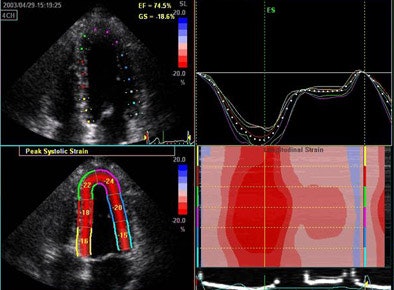

There are also new techniques for LV functional measurement, including myocardial strain, defined as a dimensionless index of the change in length of the myocardium. Its measurement may offer a "pure" index of regional LV function, but has been difficult to measure, according to Thomas.

| 3D echocardiography measures longitudinal strain in a normal volunteer. |

"This has previously been derived using tissue Doppler, looking at the change in velocity over space and integrating it over time," he said, showing images from a patient with -20% strain indicating fiber shortening in the long axis. Strain measurements showed a strong correlation with invasive systolic function and end-diastolic pressure measurements as well.

Still, "strain is more than just a number, it's a complex mathematical tensor that linear components that stretch in three dimensions," Thomas said, including linear strain and sheer strain, which can be followed by monitoring clusters of speckles. In one example, low-level exercise showed an increase circumference of strain in a normal volunteer from -16% to -25%. "This can now be integrated in three planes to give us the wall motion rank," Thomas said. Greenberg et al demonstrated that the Doppler-derived myocardial systolic strain rate is a strong index of LV contractility (Circulation, January 2002, Vol. 105:1, pp. 99-105).